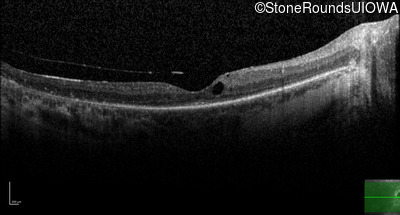

Age at visit: 53 years

This 53 year old woman first noticed night blindness at age 18. More recently she has experienced constriction of her visual fields. She has worn hearing aids since childhood.

Age at visit: 54 years